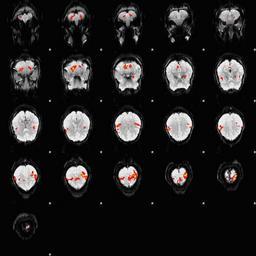

Keywords: Fingertapping experiment DXIII.jpg en An fMRI depiction of activated brain areas BOLD during an index finger-tapping sequence Experiment and imaging was performed in our dept at RIC at UTHSCSA Analysis for activation depiction was performed by me using fsl I used BET FAST and FEAT to obtain this image The experiment was performed in the following method Subjects performed a finger tapping sequence during a block design paradigm This study focused on only right hand unimanual index finger During the first 30 seconds the subjects moved their right index finger from side to side adduction-abduction at the rate of 2Hz followed by a 30 second rest period This sequence was repeated 6 times for a total of 6 minutes A Gradient-Echo planar sequence was used with the parameters of TR 2s TE 30ms and a flip angle of 90° and sixteen continuous 6mm-thick axial slices with an in-plane spatial resolution of 3mmX3mm I derived Own Zereshk This image was not published anywhere and was part of my class project Functional magnetic resonance imaging Sequence |